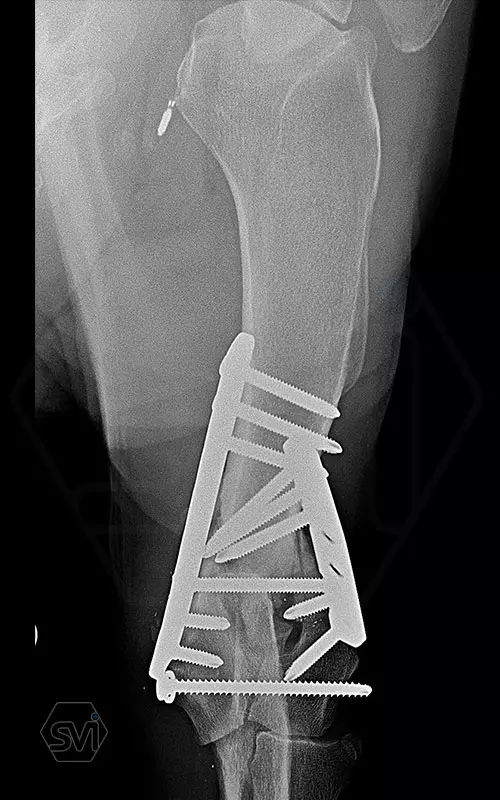

The damaged area was exposed laterally and medially, and 2 locking plate were used: a large polyiaxial straight plate made with 3.5 mm screws, and a small polyaxial plate laterally with 2.7 mm screws.

The intercondylar fragments were fixed with 3.5mm lag screw with a washer under the head.

The dog was already using his leg very nicely at control 1 month post op., barely limping. In such a case, the advantages of locking systems (distal short screws are also permanently fastened) and polyaxiality (positioning the screws of the opposing plates so that they do not interfere with each other, and avoiding the screw insertion into the joint or fracture line) are really very helpfull.